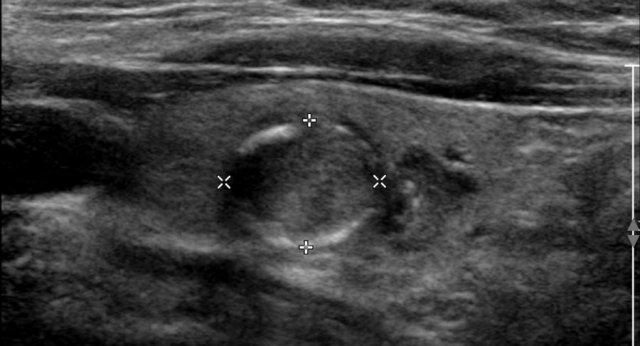

Nốt với Sự Phát Triển Ngoại Sinh

Nốt này cho thấy sự phát triển ngoại sinh với sự chèn ép các cấu trúc lân cận.

Tuy nhiên, không có bằng chứng rõ ràng về sự xâm lấn thực sự, và do đó, không đủ tiêu chuẩn để xác định là xâm lấn ngoài tuyến giáp.